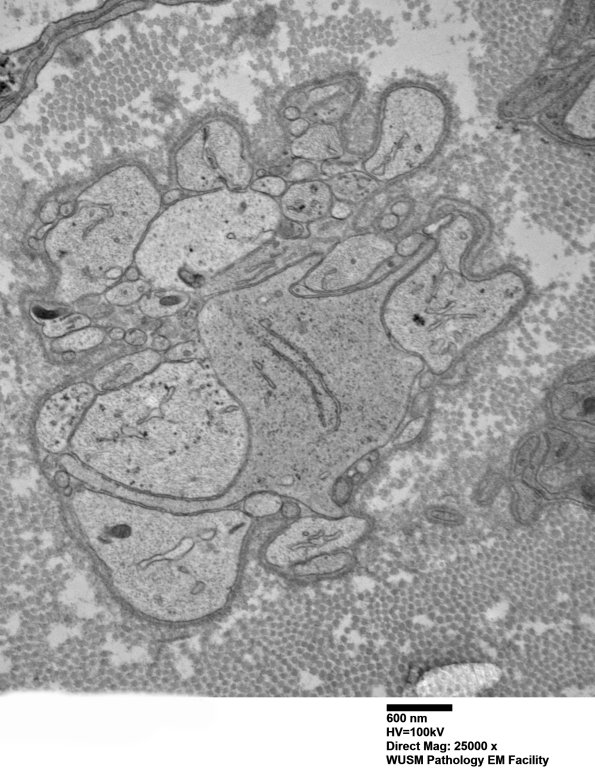

9D1,2 These are Schwann processes forming bands of Büngner. In some cases Schwann cells are enlarged and occasionally dilated with pale cytoplasm, mimicking demyelinated axons in plastic sections. (electron micrographs)